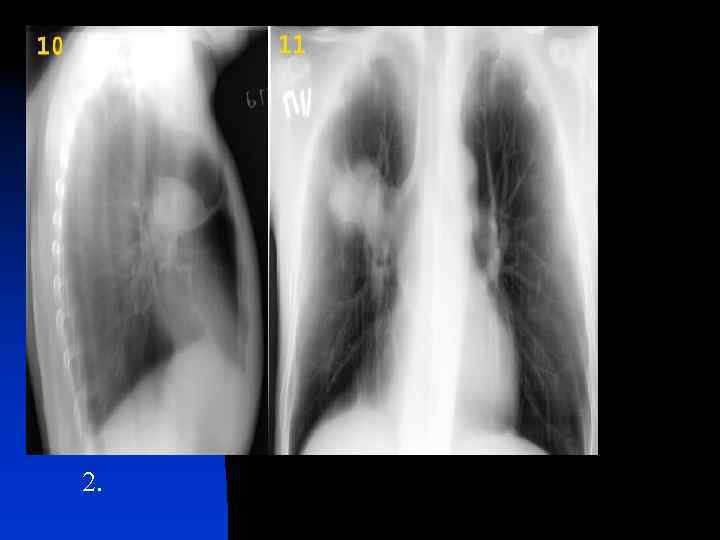

2.